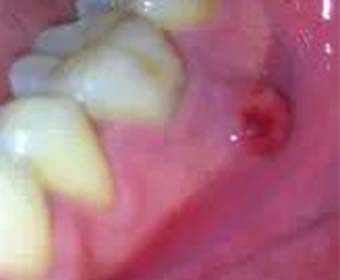

乳牙嚴重齲齒導致細菌感染輕則引起牙齦囊腫,

更甚者可能引起全身性蜂窩組織炎, .